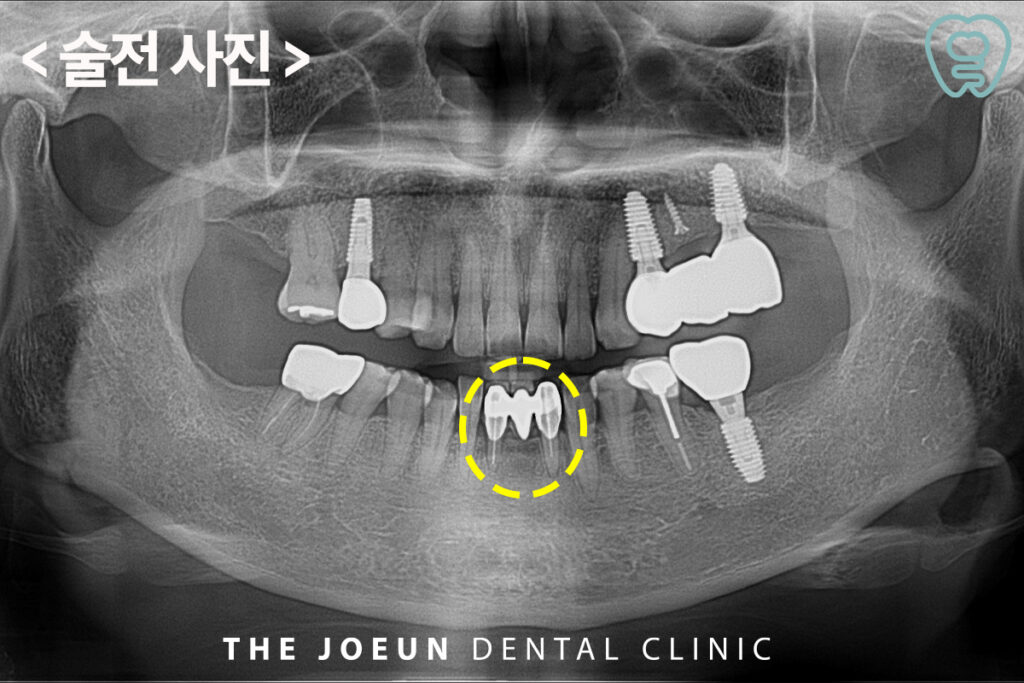

오늘은 신경치료 후 크라운이 되어 있는 아래 앞니를 발치하고 즉시 임플란트 식립을 진행하신 환자분을 소개해 드리려고 합니다.

환자분께서는 오래 전 씌워둔 아래 앞니 잇몸이 좋지 않은 것 같으시다며 피도 나고 가끔 흔들리는 느낌이 든다고 말씀해 주셨는데요. 이미 신경치료가 되어 있는 치아였기 때문에 살려서 쓰시기에는 발치 후 임플란트 식립을 진행하기로 계획을 수립하였습니다.